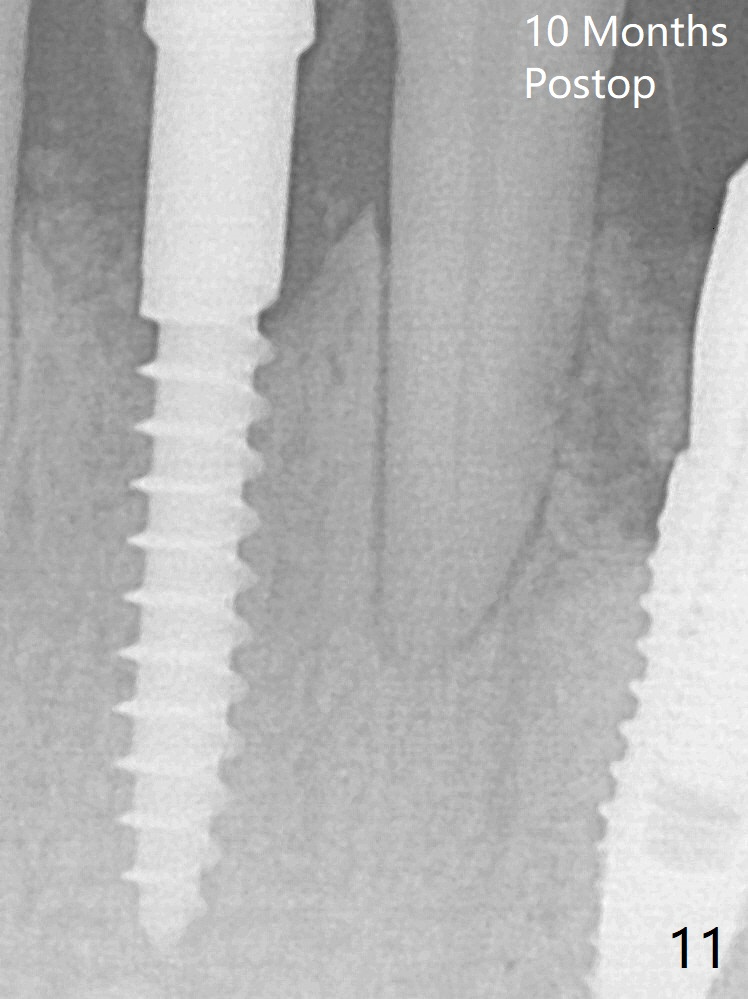

Because of the narrow flat ridge buccolingually, a 2.5x12(4) mm 1-piece implant is placed with >40 Ncm (Fig.8). With deeper placement of the implant, Vanilla graft is placed in 2 steps (Fig.9,10 *). No implant threads are exposed 10 months postop (Fig.11).